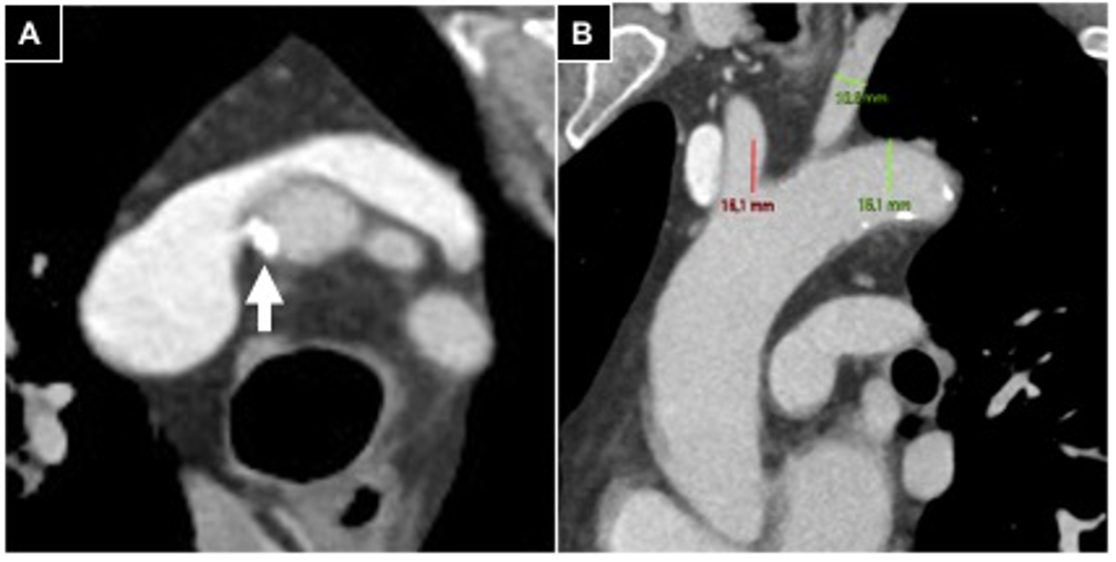

2.2. Pre-Procedural Clinical Evaluation